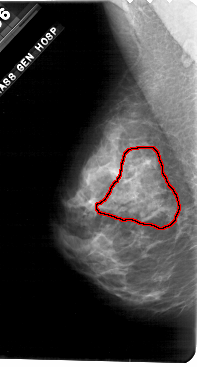

A_1698_1.LEFT_MLO

FILE: A_1698_1.LEFT_MLO.OVERLAY

TOTAL_ABNORMALITIES 1

ABNORMALITY 1

LESION_TYPE CALCIFICATION TYPE PLEOMORPHIC DISTRIBUTION SEGMENTAL

ASSESSMENT 5

SUBTLETY 4

PATHOLOGY MALIGNANT

TOTAL_OUTLINES 1

BOUNDARY